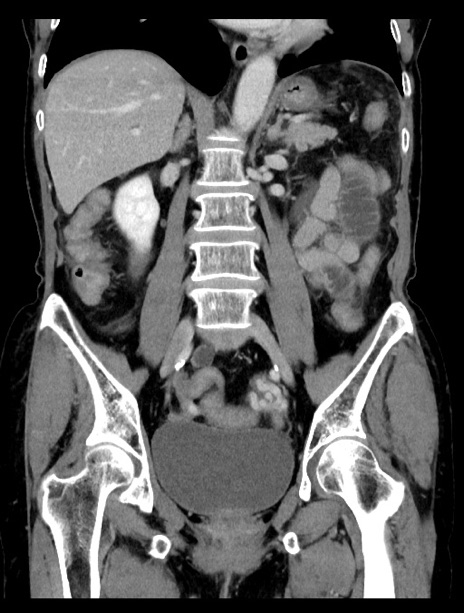

横断像

【症例】70歳代女性

【主訴】下腹部痛・嘔吐

【現病歴】2日前より腹痛あり。昨日嘔吐あり。症状改善しないため来院。

【既往歴】胃GISTに対して胃部分切除後。

【身体所見】BT 37.1℃、BP 128/77mmHg、腹部:平坦・軟、下腹部に圧痛あり。

【データ】WBC 10200、CRP 0.31